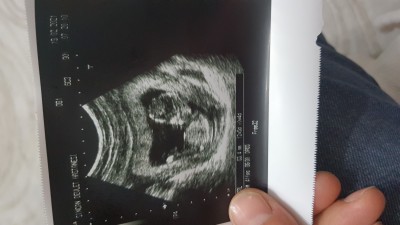

İlk gebeligim olduğu için çok merak ediyorum. 12+5 iken doktorum soylemedi. 14. Haftadan sonra söylerim dedi. Nup teorisine göre yada deneyimli anneler bir yorumlar mi?

image

Ben kız gibi hissettim kuzum

Yatışa bak :) tam bi herif yatışı ahahhs bana erkek göründüüüüü. Hayırlısı olsun sağlıklı olsun❤️

Pek keyfçi bence erkek canım hakkınızda hayırlısı olsun inşallah :)